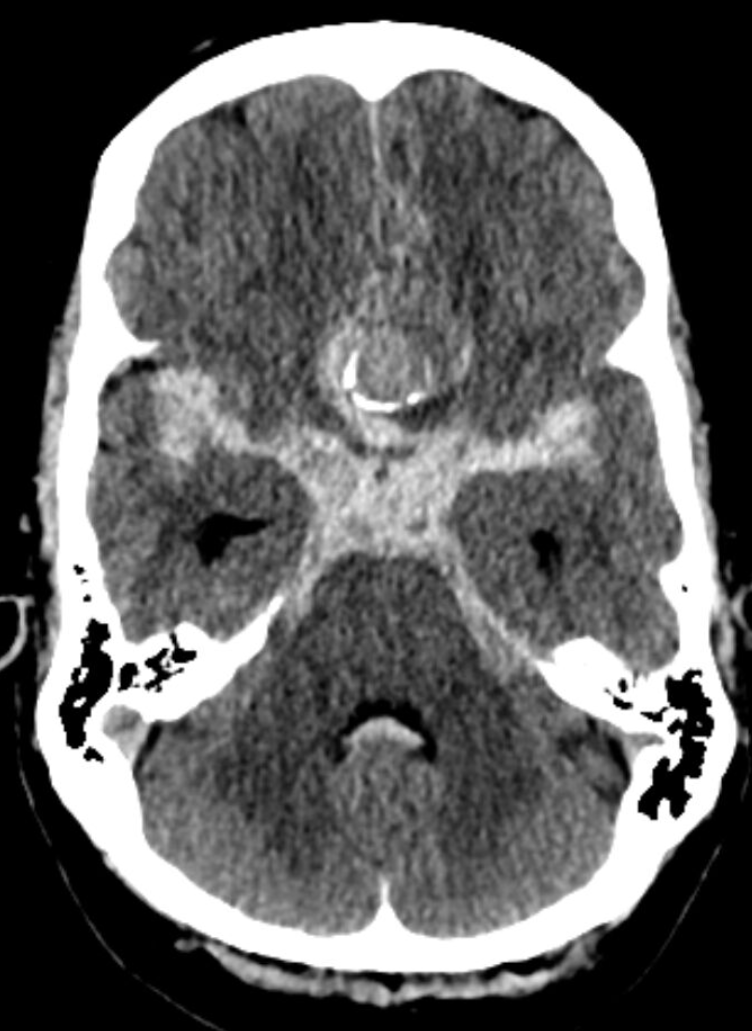

Vaikka potilaiden kliininen vointi oli erinomainen, tutkimuksessa tehdyt herkät diffuusiomagneettikuvaukset (DWI) paljastivat uusia, pieniä iskeemisiä eli hapenpuutteesta johtuvia muutoksia 63 prosentilla potilaista. Valtaosa näistä oli oireettomia, mutta ne olivat yhteydessä kohonneeseen riskiin saada ohimeneviä neurologisia oireita. Tulos osoittaa, että perinteiset toimintakyvyn mittarit eivät tavoita kaikkia hoidon vaikutuksia aivoihin.

”Aneurysmahoidossa on pyrittävä täydelliseen iskemian välttämiseen. Emme voi tyytyä mittareihin, jotka eivät tunnista hoidon aiheuttamia piileviä vaurioita”, sanoo neurokirurgian dosentti Miikka Korja.

miikka.korja@hus.fiKuvat